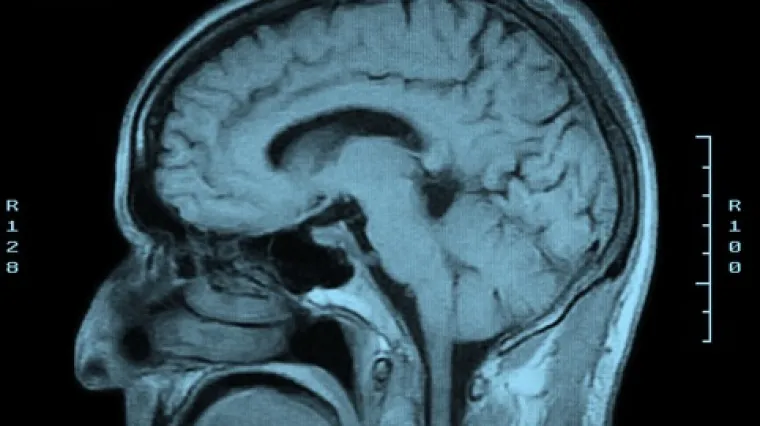

Članovi obitelj Marsili su pravi superjunaci. Šestero njih iz te talijanske obitelji ima rijetku gensku mutaciju zbog koje imaju izuzetno nisku osjetljivost na bol, što znači da su lomili kosti i dobivali razne druge bolne ozljede bez da su i osjetili. Uz to, mogu bez problema jesti i najljuće feferone. Znanstvenici su nedavno proučavali ovu fascinantnu obitelj kako bi razumjeli odgovorne gene te možda i stvorili nove metode ublaživanja boli, piše IFLScience.

Živci postoje, ali ne rade

"Članovi ove obitelji mogu zadobiti opekline ili slomiti neku kost bez da osjete ikakvu bol. Ipak, imaju normalnu intraepidermalnu gustoću živčanih vlakana, što znači da su svi živci tamo, ali jednostavno ne rade kako bi trebali", izjavio je voditelj istraživanja dr. James Cox sa Sveučilišnog koledža u Londonu. "Radimo na tome kako bismo bolje razumjeli zašto ne osjećaju bol, da vidimo kako bi se to moglo iskoristiti u novim trertmanima za olakšanje boli."